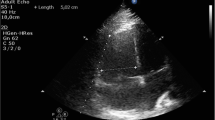

A 33-year-old Asian woman, in her third aterm pregnancy, ASA 2 with severe preeclampsia, was admitted to the ICU after caesarian section and tubectomy surgery due to shortness of breath and chest discomfort. The patient has a past medical history of severe preeclampsia in two previous pregnancies but no history of PPCM nor history of PPCM in her family, the patient also denied any history of congenital heart disease and history of heart failure. Her vital signs on ICU arrival were: blood pressure 136/92 mmHg, heart rate 150 beats/min, respiratory rate 38–40 breaths/min, temperature 38 ºC, saturation 95% with simple mask oxygen flow 6 L/min. She was awake and alert and was in a diaphoretic and tachypneic state. Lung examination revealed wet crackles throughout both lung fields. Her abdomen was diffusely tender. She had pretibial pitting edema. The neurologic examination yielded no abnormalities. Laboratory investigations at admission revealed white blood cell count was 20.300/mm3, hemoglobin and hematocrit were 13.6 g/dL, and 41% subsequently. Arterial blood gas analysis values on oxygen 6 L/min results were: pH 7.43; PaCO2 27 mmHg; PaO2 122 mmHg; PaO2/FiO2 ratio of 244; HC\({\text{O}}_{3}^{ - }\) 17.7 mmol; BE − 3 mmol/L; SaO2 98%. PT and aPTT were within normal limits, but the D Dimer value was increasing by 1999 ng/mL. Serum Na+ was 137 mmol/L; K+ 3.5 mmol/L; calcium total 9.9 mg/dL; ureum 25 mg/dL; creatinine 0.4 mg/dL; SGOT and SGPT within normal limits but her bilirubin values were increased (total 3 mg/dL; direct 2.5 mg/dL, indirect 0.5 mg/dL) and lactate 3.3 mmol/L. The electrocardiogram (ECG) showed sinus tachycardia with nonspecific ST-T wave changes. The chest X-ray examination showed cardiomegaly with increased interstitial markings (Fig. 1). Echocardiography revealed all chamber dilation with marked global hypokinesis, decreased systolic function of left and right ventricles, mild–moderate mitral regurgitation, with an ejection fraction of 22% (Fig. 2).

PPCM is characterized by dysfunction in the left ventricle and the development of heart failure [2, 3, 7]. In our case, the diagnosis criteria for PPCM were fully met. The left ventricle loses its normal contractile ability, leading to a compromised pumping function that hinders the heart's capacity to supply adequate blood flow and sustain sufficient oxygen delivery to meet the tissue's demand. This is primarily due to a decrease in cardiac output. Heart rate and stroke volume determine cardiac output, whereas the preload, contractility, and afterload determine the stroke volume [11,12,13]. In cases of low cardiac output, adjustments are made either in heart rate or stroke volume to ensure proper perfusion. If maintaining stroke volume becomes challenging, an increase in heart rate occurs to sustain cardiac output. In the observed patient, elevated sympathetic activity, indicated by vital signs, stimulated this response. Simultaneously, the cardiovascular system reacts to inadequate perfusion by activating the renin-angiotensin system, aiming to boost preload through salt and water retention, intensify vasoconstriction (thereby increasing afterload), and enhance cardiac contractility [11,12,13]. While this response is initially effective, prolonged activation leads to the loss of myocytes and adverse changes in surviving myocytes and the extracellular matrix. The myocardium, continuously exposed to stress, undergoes remodelling and dilation as a reaction to the insult. Remodelling further contributes to cardiac decompensation and gives rise to complications such as mitral regurgitation, caused by stretching of the valvular annulus. This complication was also evident in the echocardiography of the patient [11,12,13].